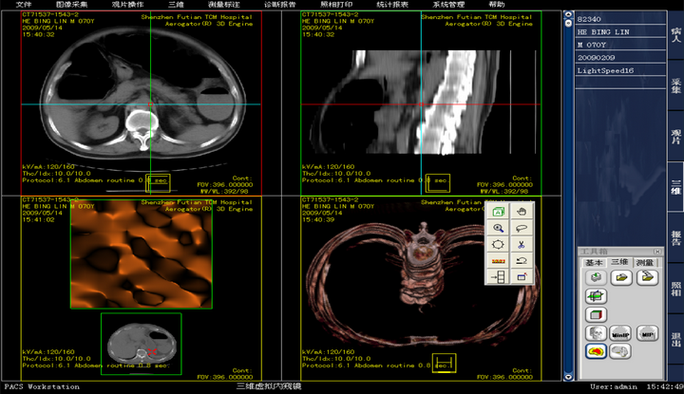

1. 虚拟内窥镜技术:利用计算机图形学、虚拟现实、图像处理和科学可视化等技术,模拟真实光学内窥镜对病人进行诊断的一种技术。VE(虚拟内窥镜),CT重建图。

VE(Virtual Endoscopy),虚拟内镜技术。这种CT重建图像可以模拟各种内镜检查的效果,它是假设视线位于所要观察的管“腔”内,通过设定一系列的参数范围,即可看到管“腔”内的结构。

对原始图像进行分割,分割出目标图像–三维重建技术将二维目标图像重建为三维立体形态–路径提取算法提取出三维立体形态中的中心路径–设置虚拟相机沿着提取的中心路径完成对三维立体形态内部结构的漫游。